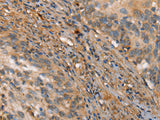

Applications IHC

IHC 1:50-1:200